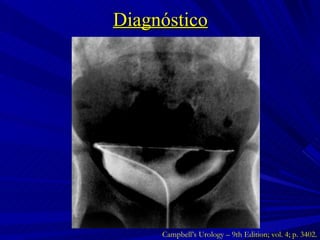

Diagnóstico Campbell’s Urology – 9th Edition; vol. 4; p. 3402.